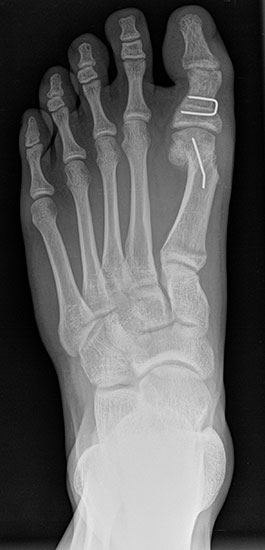

Bei einem juvenilen Hallux valgus handelt es sich um eine schon im Kindes – oder Adoleszentenalter 1 bestehende Valgusdeviation der großen Zehe bei Spreizfuß mit vergrößertem Intermetatarsalwinkel I / II aufgrund einer Adductionsstelllung des Metatarsale I – Metatarsaus primus varus.

Davon abzugrenzen ist der Hallux valgus interphalangeus ohne zugrundeliegenden Spreizfuß. Hierbei handelt es sich um eine Fehlstellung des Grundgliedes bei dem der mediale Anteil länger ist als der laterale und dadurch die distale Gelenkfläche des Grundgliedes am Endgelenk valgisch steht. Das Grundgelenk steht orthograd. Möglich ist darüber hinaus eine Kombination aus einer Hallux valgus Fehlstellung mit Hallux valgus interphalangeus Deformität.

Im Gegensatz zum Hallux valgus des Erwachsenen ist die Valgusabweichung der großen Zehe meist geringer ausgeprägt als bei Erwachsenen, der Intermetatarsalwinkel oft stark vergrößert. Die Angaben ab wann der Intermetatarsalwinkel als vergrößert gilt schwanken zwischen > 9° 2 und >14°3. Das Ausmaß der Beschwerden korrelieren nicht mit dem Auftreten und dem Schweregrad der Deformität (Zollinger 1990, Zollinger 1993). Begünstigend wirkt eine Schrägstellung des ersten Tarsometatasalgelenkes (Hefti 1998) und eine Hypermobilität dieses Gelenkes 2 in Kombination mit einer Bindegewebsschwäche. Häufig liegt eine positive Familienanamnese vor. In einer Untersuchung von Coughlin fand sich eine Vererbung über die mütterliche Linie in 72%, ein milder bis stark ausgeprägter Knick-Senkfuß in 17% (das entspricht der Quote von Knick-Senkfüßen in der Normalbevöl­kerung) aber in 22% ein Pes adductus, das ist wesentlich mehr als in der Normalbevölkerung zu erwarten wäre 4. Auch für Hefti (1998) gilt der Pes adductus als Komponente des Sichelfußes als begünstigend. Zur Inzidenz des Hallux valgus juvenilis finden sich je nach Autor verschiedene Angaben. Nach Auswertung von Schuluntersuchungen liegt die Häufigkeit zwischen 1,6 % bis 17% 56. Häufig tritt die Fehlstellung doppelseitig auf. Der Anteil der betroffenen Mädchen liegt 4-5x höher als bei Jungen (Lamprecht 2015).

Auch einige Syndrome gehen mit der Ausbildung eines ausgeprägten Spreißfuß mit Hallux valgus einher. Auf der Abbildung ein junger Erwachsener mit Trisomie 21.

Standard ist die belastete Röntgenaufnahme des Fußes dorso-plantar und seitlich. Günstig ist eine Röhrenkippung von 10°-20°, um die Gelenke der Lisfranc-Linie einsehen zu können.

• Hallux valgus Winkel

• Hallux valgus interphalangeus Winkel

• Intermetatarsalwinkel I zu II

• Distaler Metatarsale Gelenkwinkel (PASA)

• Form des Mittelfußknochenkopfes

• Winkel Metatarsale I Basis zum Os cuneiforme mediale

• Metatarsalindex

• Elevation/ Plantarisierung I. Strahl

• Pes metatarsus adductus

• Wachstumsfugen